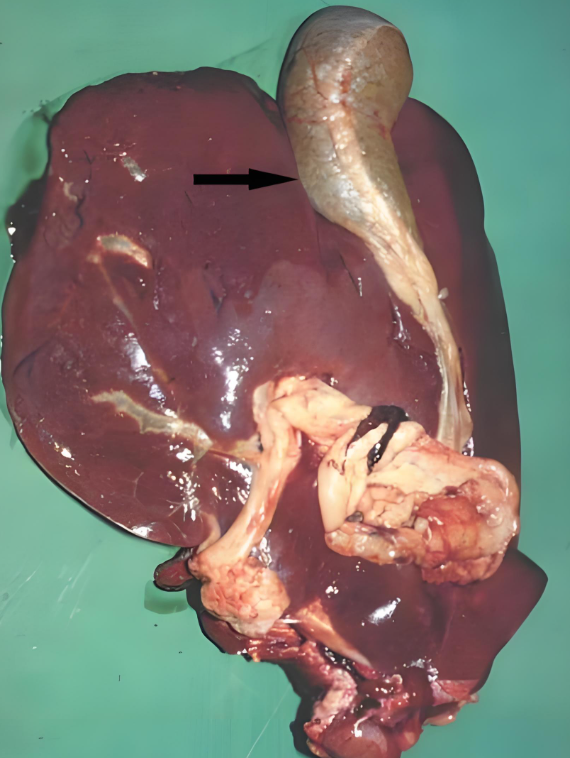

对牧区和低洼地带的养殖户来说,牛羊肝片吸虫病是常年悬着的 “隐患”—— 它不仅是牛羊的 “健康杀手”,导致消瘦、产奶下降甚至死亡,还是人畜共患病,人若生食受污染的水生植物、鱼虾也可能感染。掌握这种病的 “识别 - 防控 - 治疗” 全流程,是养殖户减少经济损失、保障养殖安全的关键。本文结合临床实践,拆解牛羊肝片吸虫病的科学应对方案,让养殖户能 “看得懂、用得上”。

肝片吸虫病的发生有明显规律,症状也分急慢性,只有摸透这些特点,才能在发病初期及时干预。

2. 症状:急慢有别,这些 “信号” 别忽视

肝片吸虫病的症状分急性、慢性和典型表现,不同阶段症状差异明显,需针对性判断: